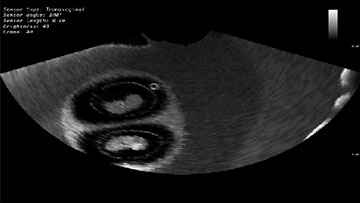

Симулятор ультразвуковой диагностики MedVision SonoVision

Виртуальный симулятор ультразвуковых исследований (УЗИ) SonoVision – обучающий тренажер на единой платформе обеспечивающий освоение основных навыков проведения ультразвукового исследования, понимание и идентификацию различных заболеваний и патологии внутренних органов человека.

SonoVision – симулятор ультразвуковой диагностики является инструментом для профессионального изучения медицины. Это виртуальный симулятор для отработки навыков ультразвуковой диагностики. Он используется как студентами, так и практикующими специалистами в клиниках и больницах. Симулятор ультразвуковой диагностики – прекрасное дополнение к традиционному обучению и повышению квалификации медицинского персонала.

Новое поколения симулятора УЗИ гарантирует высочайший уровень детализации внутренних органов, а работа с анатомически корректным манекеном обеспечивает реалистичные тактильные ощущения и визуальную картину при выполнении вмешательств. В симуляторе реализовано более 40 клинических сценариев.

Модуль по исследованию плода на первом триместре развития

- Обучающий модуль "Акушерство на 1-м триместре развития"